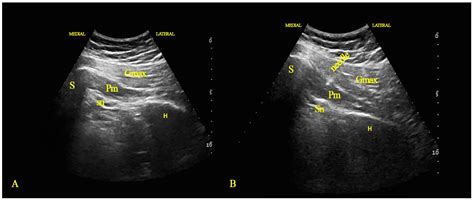

Not all ultrasounds are the same. Depending on the stage of pregnancy and what the doctor needs to investigate, they may choose different modalities:

| Transabdominal | Transducer moved over the belly | General viewing and anatomy checks |

| Transvaginal | Probe inserted into the vagina | Early pregnancy visualization |